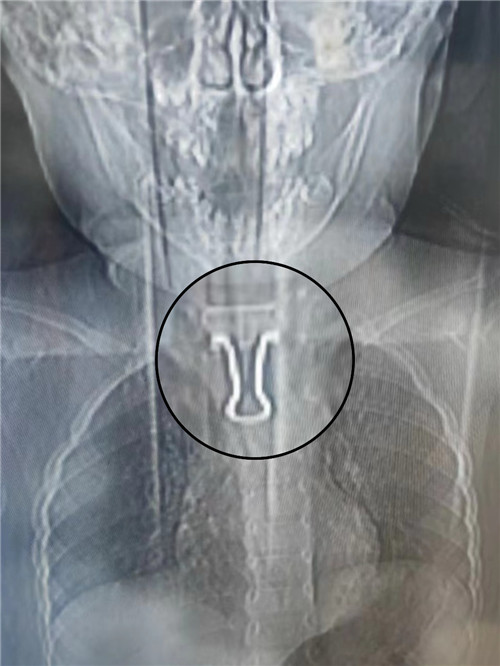

CT檢查結(jié)果顯示,燕尾夾金屬面朝上,尾柄接近心臟主動(dòng)脈弓,卡在食管里。金屬夾邊角尖銳,易劃傷食管,且幼兒食管入口比成人窄,很難取出。在綜合評(píng)估病情后,耳鼻咽喉頭頸外科團(tuán)隊(duì)決定迎難而上,立即施行食管鏡食管異物取出術(shù)。

“異物位置太刁鉆了!”為了不傷到幼兒食管“一絲一毫”,科室團(tuán)隊(duì)全程半蹲手術(shù),小心翼翼反復(fù)嘗試了多種工具,終于成功將異物取出,幼兒轉(zhuǎn)危為安,現(xiàn)已出院。